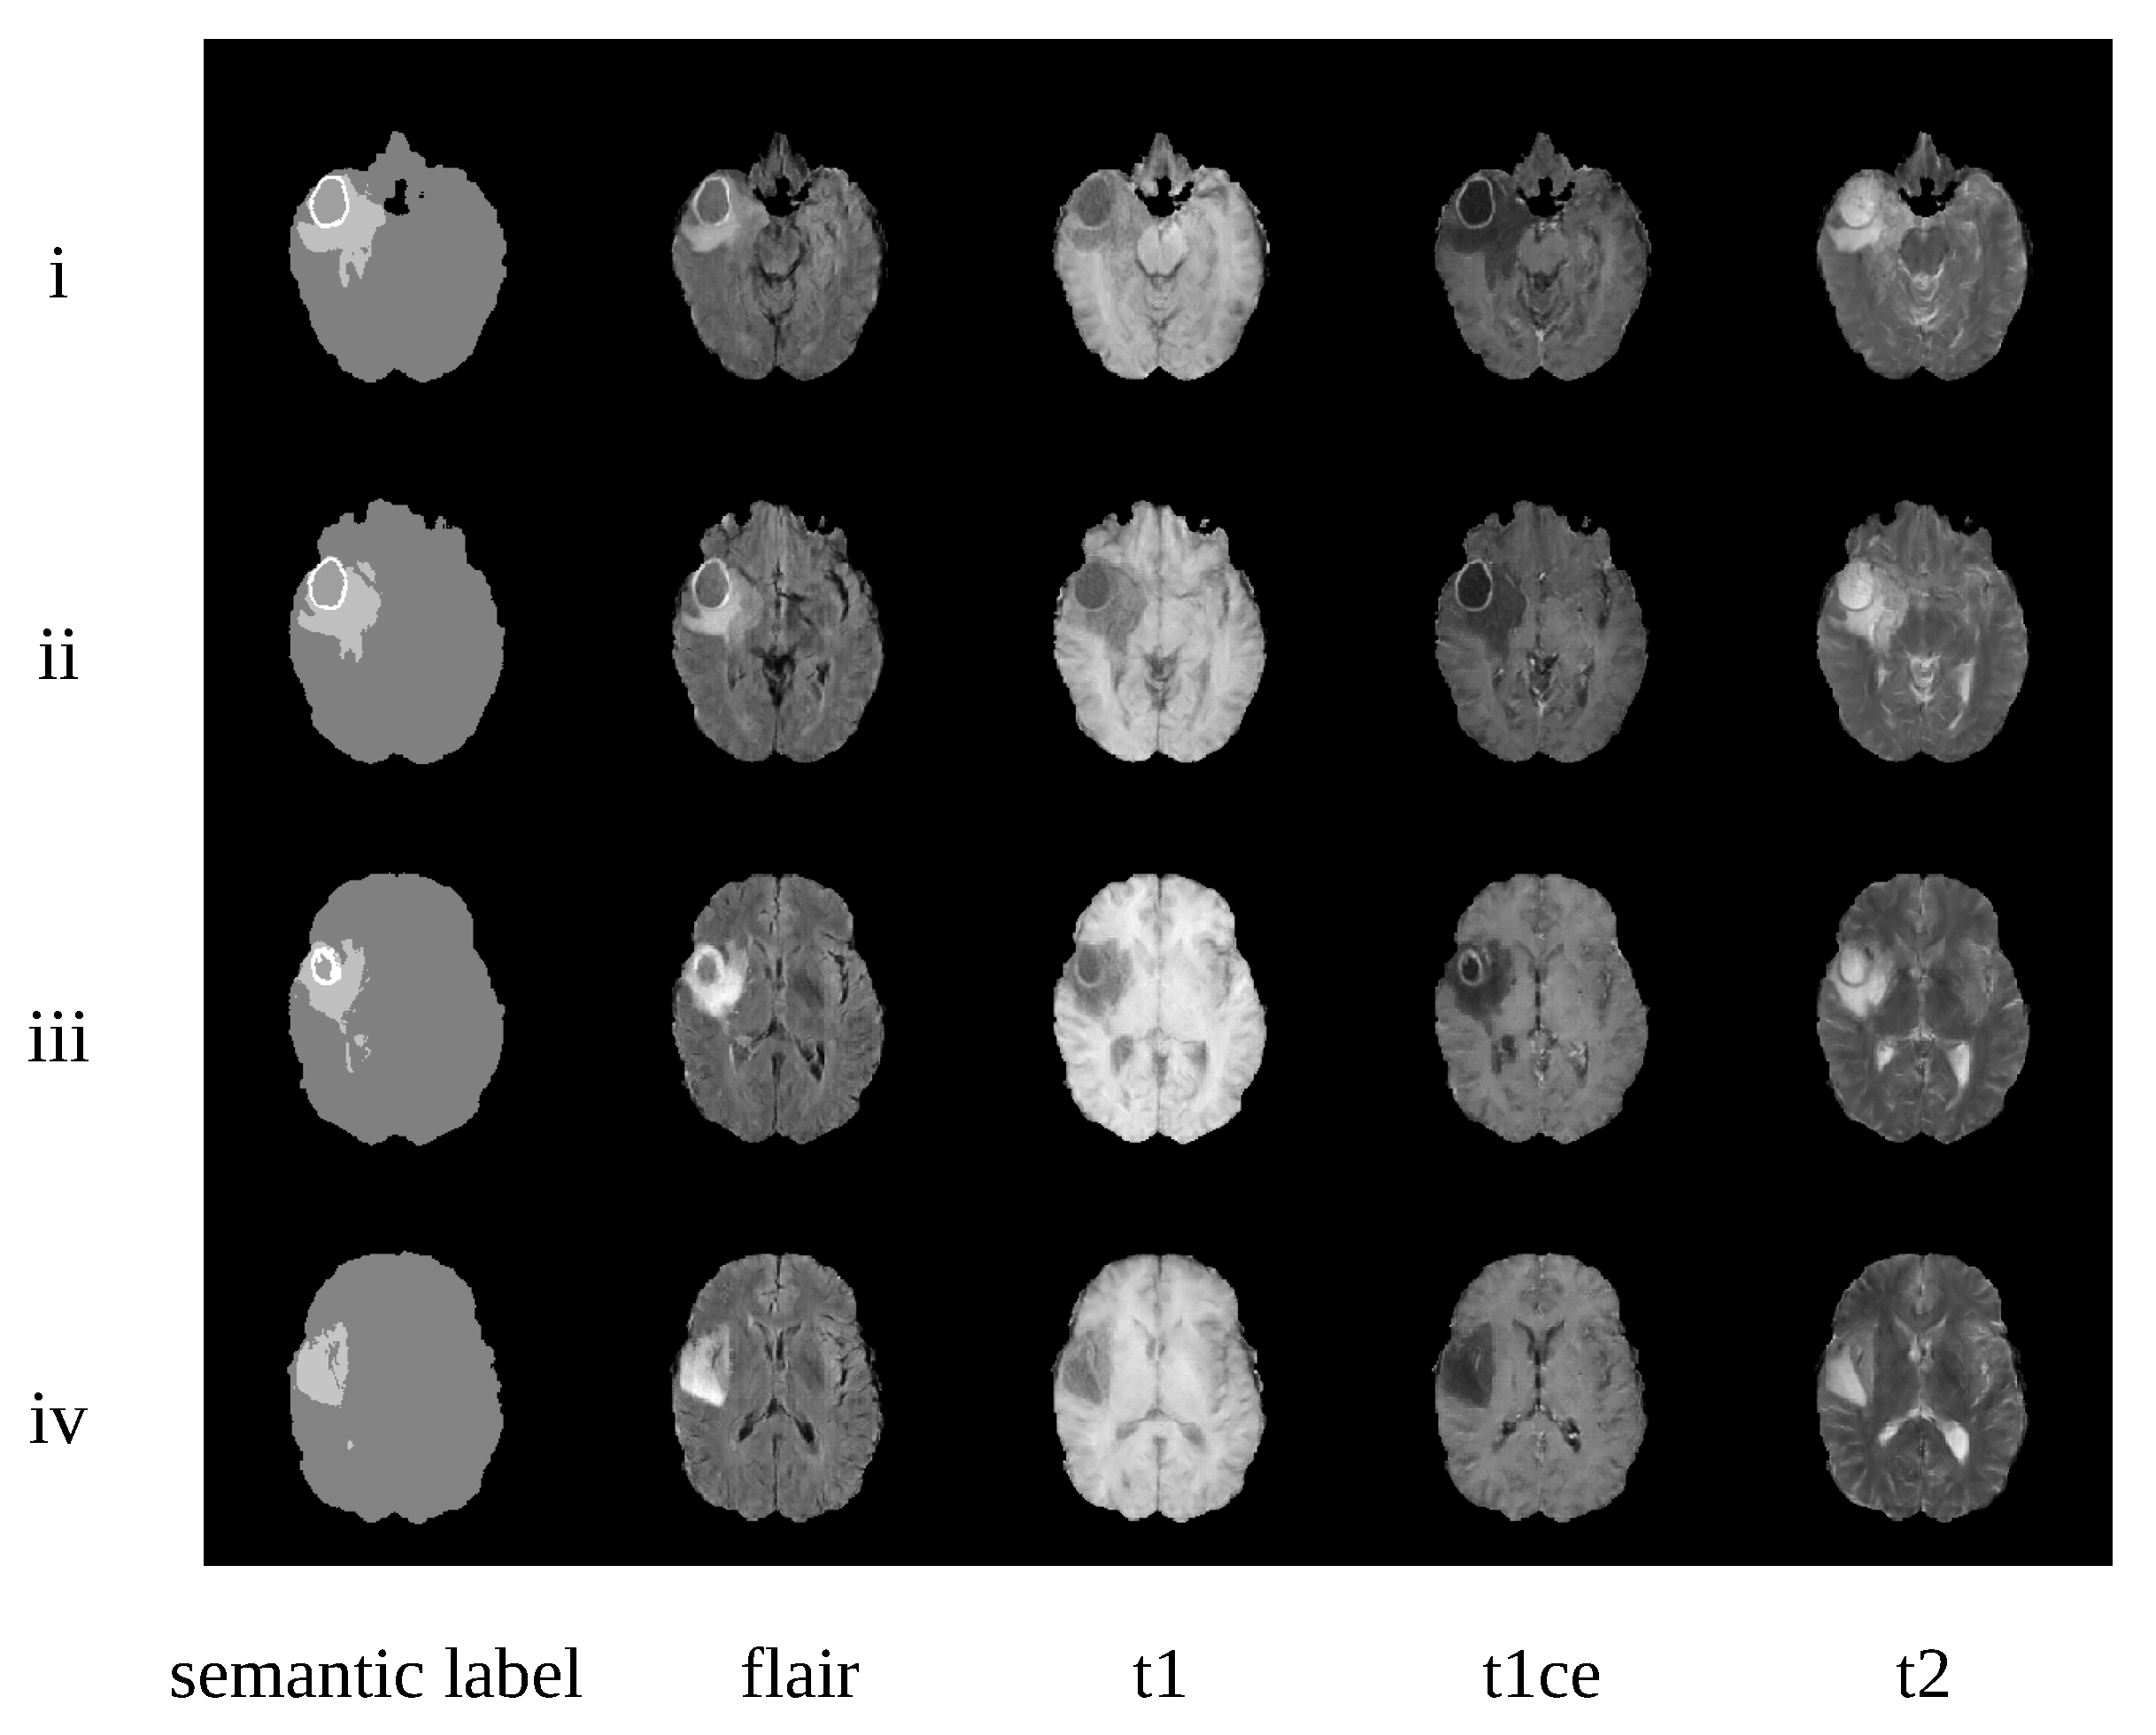

4.3. Qualitative Evaluation